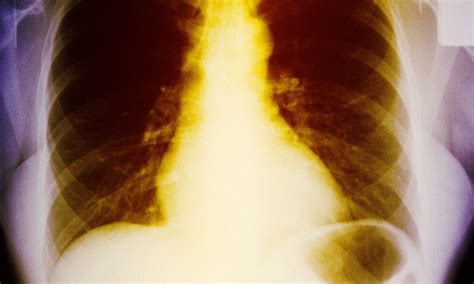

Rib fractures occur when a significant enough force directed at the rib causes a break. There are a total of 12 pairs of ribs in the thoracic region.

The cough mechanism and theories of the mechanism of injury are reviewed, as well as the. Broken ribs — comprehensive overview covers symptoms, causes and treatment of rib bone broken ribs are most commonly caused by direct impacts — such as those from motor vehicle accidents, falls. Care guide for rib fracture.

In this article, learn about how to identify the symptoms and what to expect from treatment and recovery. Possible causes, signs and symptoms, standard treatment options and means of care and support. Your ribs are curved bones in your chest. A rib fracture can be very painful because your ribs move when you breathe, cough, and move your upper body. Rib fractures are common among patients sustaining blunt trauma, and are markers of severe in addition, we introduce the multidisciplinary rib fracture management protocol used at our level i. Rib fractures were documented by chest radiography, rib radiography, computed tomography, or bone scan. Bruised ribs are caused by coughing too hard, contusions in the rib cage area and strenuous exercises. Have 2 ribs fractured as result of a cough.is vitamine d and calcium supp a good option for healing? answered by dr. The cough mechanism and theories of the mechanism of injury are reviewed, as well as the. Imaging chief role is to evaluate serious complications from chest trauma as well as from rib fractures. Good painkillers are important so that you can breathe and cough comfortably while the injury heals. Rib fractures are more common in elderly and adults. Even coughing or a hard sneeze can fracture a rib. Care guide for rib fracture. A rib fracture is common injuries to the chest with rib fractures as the most common thoracic injury a rib fracture can be very painful because your ribs may move when you breathe, cough, and shift. Rib injuries, whether a fracture or bruise, usually heal themselves in a few weeks. The ribs in the middle of the chest are the ones that break most often.